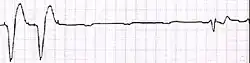

Exemplo de ECG do dispositivo a) flutuando livremente no VD b) em contato com a parede do VD

Exemplo de ECG do dispositivo a) flutuando livremente no VD b) em contato com a parede do VD -